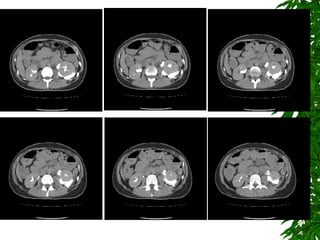

L't Percutaneus nephrostomy (PCN) (Day 6) 1. Tear of infeior wall of the extra-renal portio of L't renal pelvis, with contrast media extravasating out to L't peri-renal extraperitoneal space. 2. L't hydronephrosis and L't hydroureter. 3. L't PCN done successfully, with a 8 Fr pig-tail drainage catheter placed in the L't renal pelvis with good drainage function. Arrange cystoscopy tomorrow (Day 7) due to clear urine drained from PCN tube.

L't Percutaneus nephrostomy(PCN) (Day 6) 1. Tear of infeior wall of the extra-renal portio of L't renal pelvis, with contrast media extravasating out to L't peri-renal extraperitoneal space. 2. L't hydronephrosis and L't hydroureter. 3. L't PCN done successfully, with a 8 Fr pig-tail drainage catheter placed in the L't renal pelvis with good drainage function. Arrange cystoscopy tomorrow (Day 7) due to clear urine drained from PCN tube.